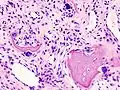

Annotated illustration of healthy hip joint

Healthy hip joint

Annotated illustration of hip joint with osteoarthritis

Hip joint with osteoarthritis[36]